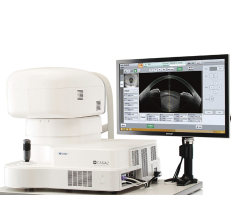

Оптический когерентный томограф Optovue Solix обладает повышенной скоростью сканирования — 120 000 А-сканов в секунду. SOLIX предоставляет множество инструментов для нового поколения борьбы с заболеваниями, которые повышают пропускную способность и обеспечивают превосходный уход за пациентами. В отличие от томографов более ранних поколений ОКТ SOLIX OPTOVUЕ может определять наличие конкрементов и новообразований сосудов сетчатки и хориоидеи, позволяет получать максимально точную послойную визуализацию структур глаза.

Преимущества

- Повышенная скорость сканирования — 120 000 А-сканов в секунду;

- Встроенная фундус-камера;

- Программное обеспечение МСТ (Motion Correction Technology) — алгоритмы сканирования для пациентов с плохой фиксацией взора;

- Диапазон сканирования в режиме ангио-ОКТ — от 3х3 до 18х18 мм;

- Размер зоны сканирования в аксиальном направлении — 6,25 мм;

- Программа AngioAnaliticsTM для количественного анализа сосудов сетчатки;

- Полноразмерное сканирование передней камеры;

- Оптическая пахиметрия, картирование эпителия и стромы роговицы в зоне диаметром 10 мм.